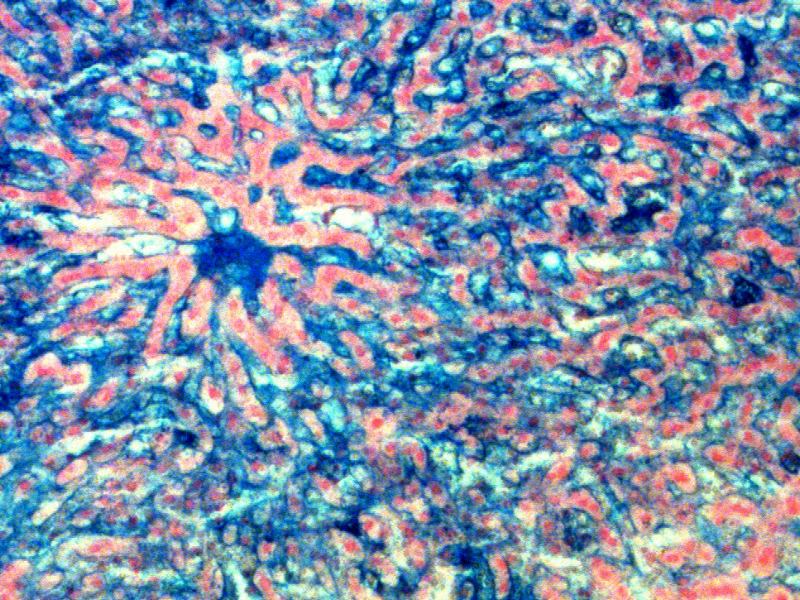

Liver Structure

3 Views of the Histology

This background theoretical knowledge, can be used to compare with the histological views as seen on a slide.

Compare the central vein and portal triad...